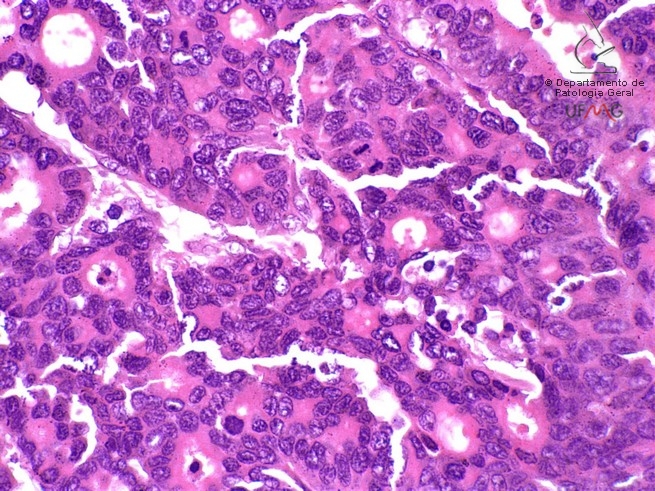

Neoplasia III 60x

Estômago

Adenocarcinoma gástrico

Coloração: HE